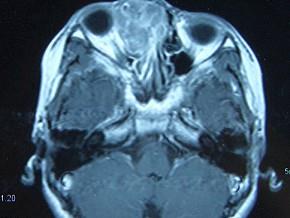

女,16岁,鼻塞、流涕一年余,失去嗅觉,影像检查如图所示,最可能的诊断是 ( )

答案: E